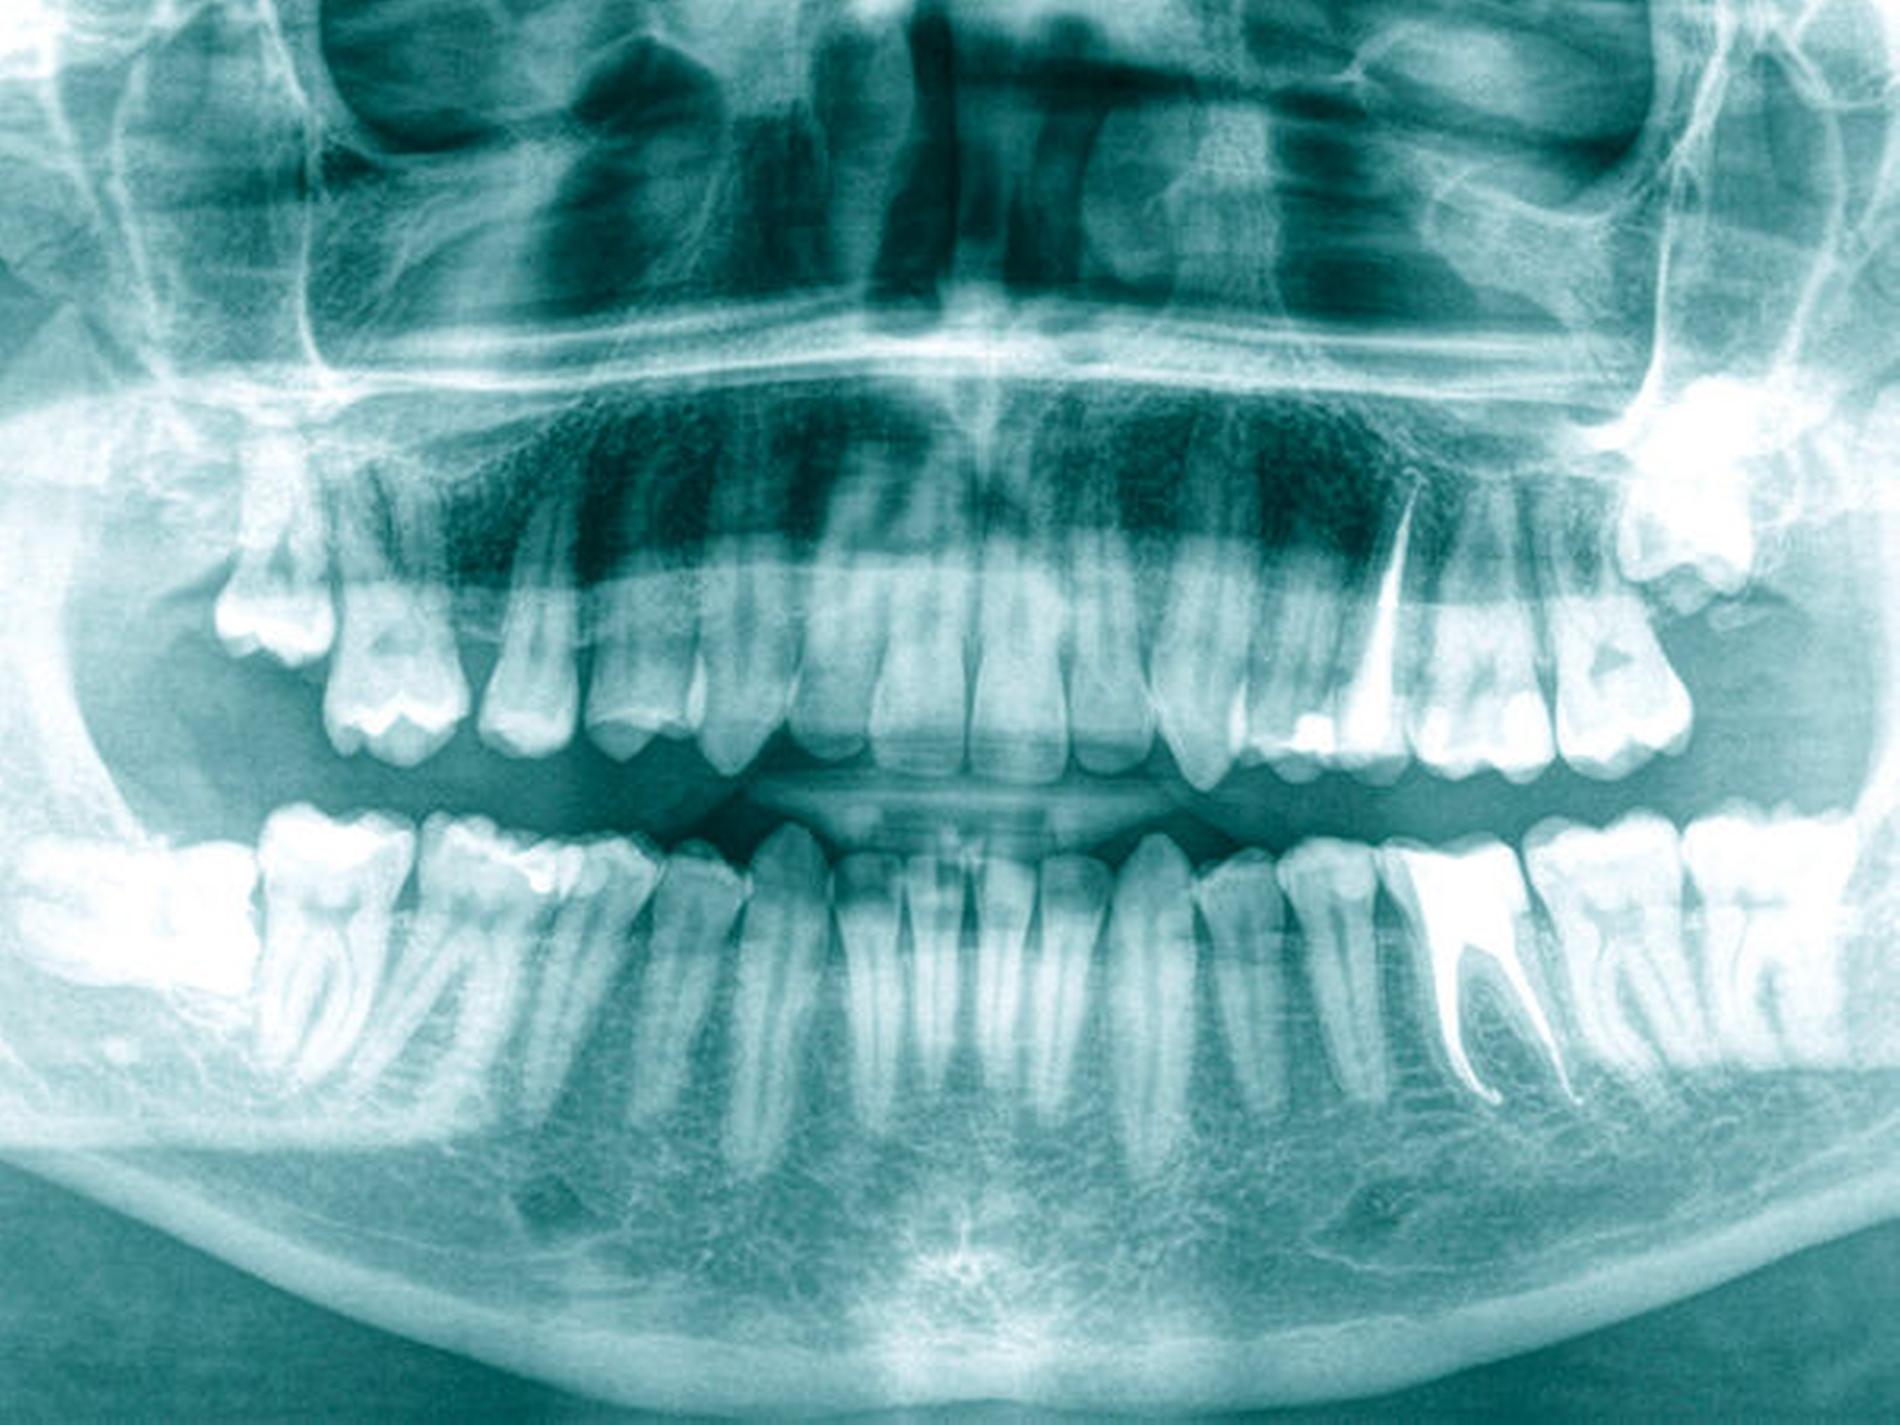

Ein 34-jähriger Patient stellte sich im August 2020 zur Wurzelkanalbehandlung an 25 und 36 und zur Versorgung kariöser Läsionen an mehreren Zähnen in der Praxis vor. Die Anamnese und der bisherige Therapieverlauf offenbarten eine hohe Kariesaktivität ab dem 25. Lebensjahr. An Molar 26 wurde klinisch und radiografisch eine profunde Karies mit deutlicher Progression mesial und distal diagnostiziert (Abbildungen 1 und 4). Gleichzeitig war der Zahn durch eine frühkindliche, metabolisch ausgelöste Hypoplasie von Schmelz und Dentin geprägt. Die Inzisivi und die unteren Molaren waren von der Anomalie nicht betroffen, stattdessen zeigten sich hypoplastische weiße Flecken an 31, 32 und 33 (Abbildung 1). Der Zahn 16 war im Alter von 21 Jahren alio loco extrahiert worden.

Bei ausgedehnten Schmelz-Aplasien können die Schmelzränder auch abbrechen – nicht weil der Schmelz hypoplastisch ist, sondern weil das hypoplastische Dentin den Schmelz nur ungenügend abstützen kann. Jedenfalls sind metabolisch entstandene Hypoplasie-Zähne mit anpassungsfähigen Restaurationen aus Composite-Materialien, Goldlegierungen und indirekten Hybrid-Composite-Materialien lebenslang erhaltungsfähig, weil die Karies einen Bogen um die Hypoplasie macht, aber vor dem normalen Schmelz und Dentin des Zahns nicht Halt machen muss.